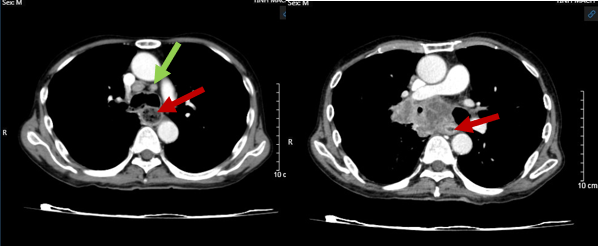

Hình 3: Hình ảnh chụp cắt lớp vi tính ngực – bụng: U phổi bên trái - Theo dõi tổn thương di căn (mũi tên đỏ), giãn phế nang 2 bên phổi (mũi tên xanh).

Hình 4: Hình ảnh chụp cắt lớp vi tính ngực – bụng: Hạch trung thất nhóm 7 (mũi tên xanh), u chèn ép thực quản gây ứ đọng dịch, thức ăn (mũi tên đỏ).

Kết luận: Hình ảnh khối u vị trí rốn phổi phải và thùy dưới phổi phải, xâm lấn nhĩ trái gây huyết khối buồng nhĩ trái, xâm lấn thực quản, cơ hoành, nhu mô gan phải. Nốt đặc rải rác phổi trái, hạch trung thất, nốt tuyến thượng thận trái – theo dõi tổn thương thứ phát. Giãn phế nang rải rác nhu mô phổi 2 bên.